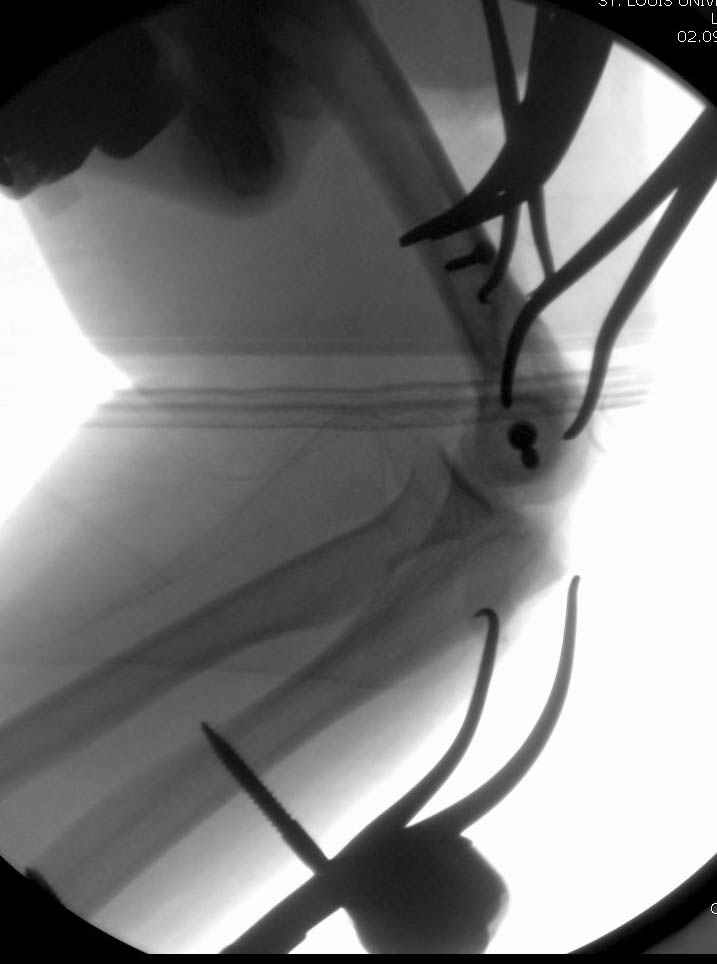

Djoldas Kuldjanov, M.D. 09 Сентябрь 2005, 20:07

Примерный случай, только перелом был открытый, в задне-медиальной стороне рана около 2 см по характеру "изнутри кнаружи", неврологический статус со слабостью сгибания мизинца, также слабая абдукция и аддукция указательного пальца и сгибания в кисти.

Больному сделали обработку и наложили временный аппарат внешной фиксации плечо-предплечье.

На шестой день сделали открытую репозицию чрезлоктевым доступом двумя locking plate, локтевой нерв был ушибленным, после операции положительная динамика в Flexor Carpi Ulnaris. Фиксацию локтевого отростка произвели tension band technique с дополнительным шурупом.

Этапы операции на снимках....